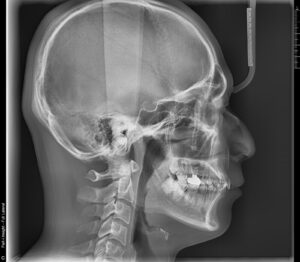

咬合(噛み合わせ)は単に歯だけの問題ではありません。姿勢や呼吸と深く繋がりがあります。

・噛み合わせの接触状態

・姿勢と骨格のバランス評価

・矯正が必要かの評価